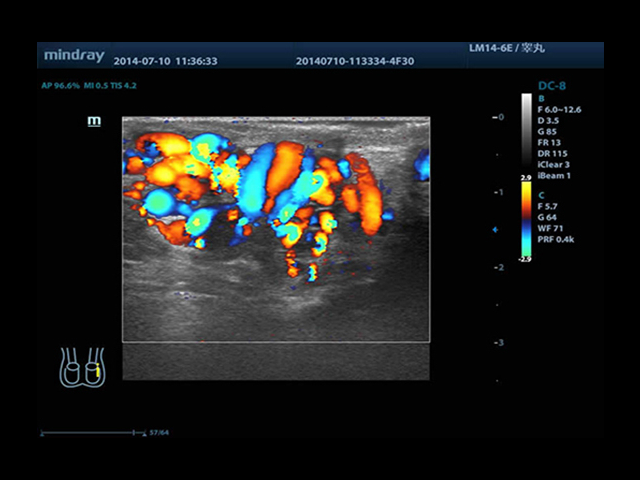

Mindray DC-8 Exp оснащен новым поколением датчиков с увеличенным количеством элементов и инновационной технологией "3T". Это позволяет достичь высокой детализации и качества изображения. Благодаря новейшей технологии iFlow, можно визуализировать даже самые мелкие сосуды и кровеносные пути.

Сверхширокополосная нелинейная обработка изображений снижает визуальные шумы на 30% по сравнению с другими системами. Технология iClear позволяет устранить зернистость изображения, а iBeam (технология пространственного компаундинга) обеспечивает высокое качество сканирования органов и тканей под различными углами.

• HR-flow™ - режим отображения кровотока с высоким временным и пространственным разрешением для точной и однородной визуализации сосудов, в том числе самых мелких

• Высокочастотный линейный датчик 38 мм Mindray l14-6NE